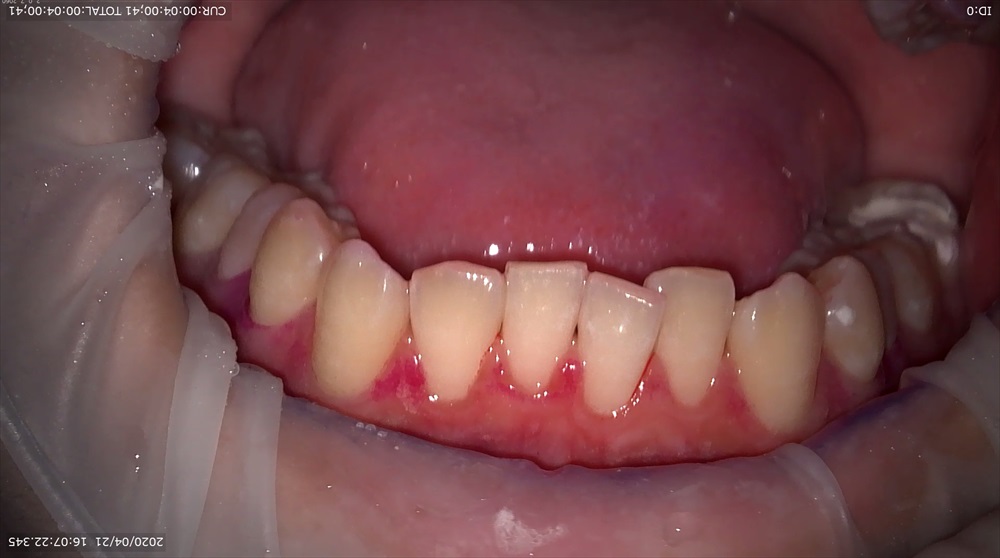

どうやって抑制していくかというと、当医院ではエアフローパウダーを使用していきます。

アミノ酸のグリシンというパウダーを使用し、歯面を傷つける事なく歯の面や歯周ポケット内にまで行き渡り除去していきます。

患者さんからはスッキリした、痛みもなく気持ちいいと言う声をいただいています!!

プレミアムクリーニングではパウダー以外にも悪玉菌の抑制を行いむし歯・歯周病予防を行っています。